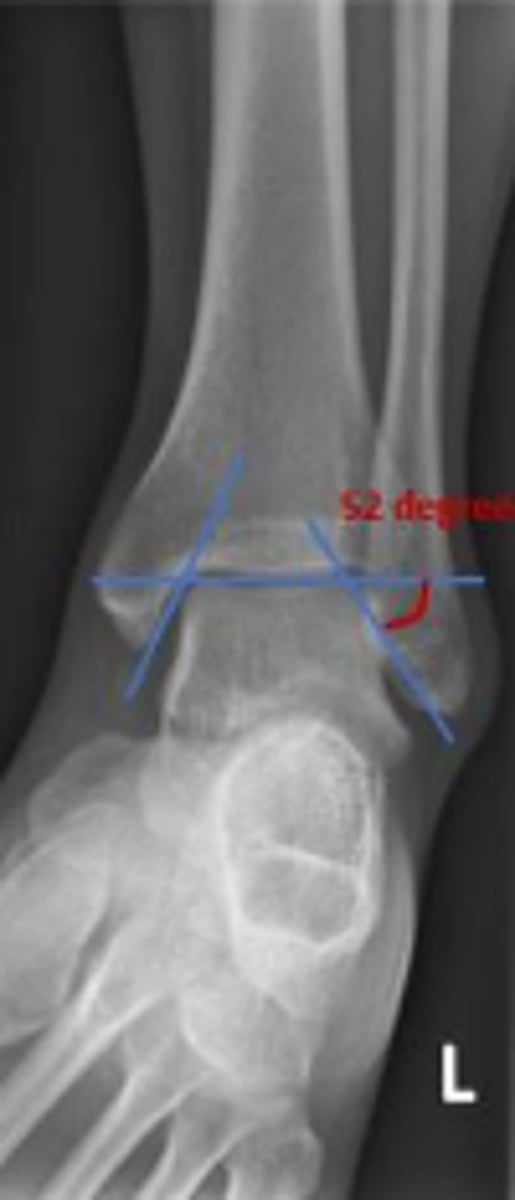

Axial relationship of the ankle

What is the overarching name of the assessment?

Tibial angle & fibular angle

What are the 2 components of the assessment?

Tibial angle

What is the name of the assessment?

Yes

Is the assessment within normal limits?

Fibular angle